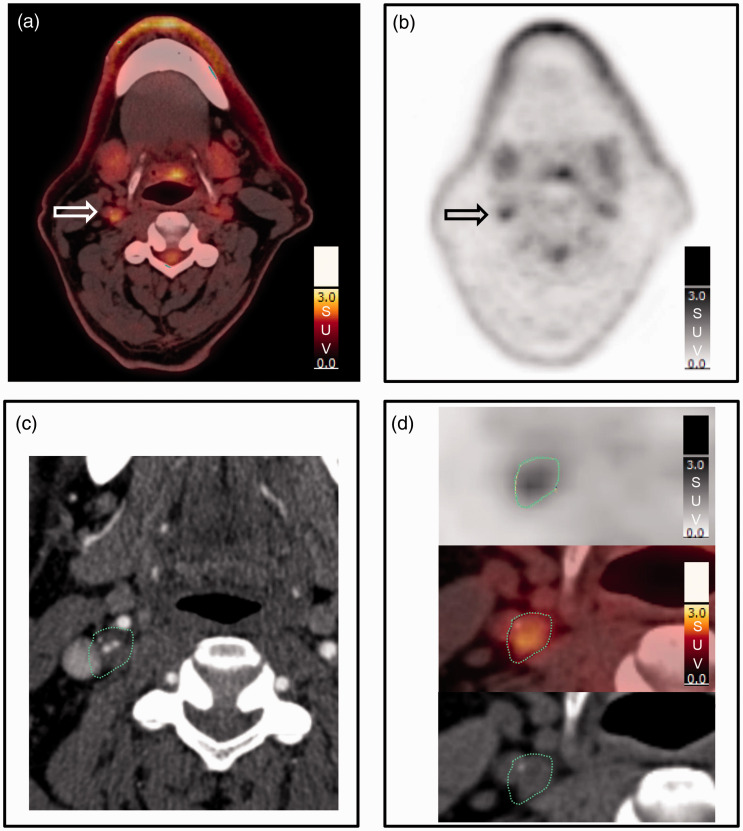

Methods: We assessed the inter-reader variability of different methods for quantification of 18F-FDG uptake in 43 patients with carotid artery stenosis ≥70%. Two independent readers delineated the plaque and collected maximum standardized uptake value (SUVmax) from all axial PET slices containing the atherosclerotic plaque.

Results: Uptake values with and without background correction were calculated and intraclass correlation coefficients were highest for uncorrected uptake values (0.97-0.98) followed by those background corrected by subtraction (0.89-0.94) and lowest for those background corrected by division (0.74-0.79).

Conclusion: Quantification methods without background correction have the highest inter-reader agreement for 18F-FDG PET of carotid artery plaque inflammation. The use of the single highest uptake value (max SUVmax) from the plaque will facilitate the method's clinical utility in stroke prevention.